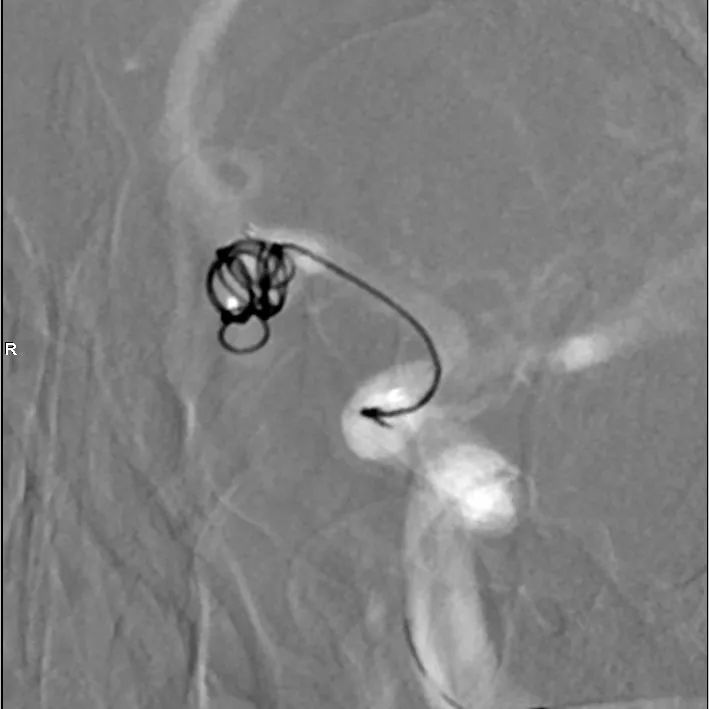

选择合适角度,分别超选支架导管、微导管。

填圈、成篮。

直接释放支架,展开良好,完全覆盖瘤颈。

换至填圈角度,继续填圈。

填塞满意,同时将微导管退出瘤颈,并解脱。

换至释放支架角度,见瘤颈处少许残留,用弹簧圈输送钢丝将微导管再次置入瘤颈,填入弹簧圈2mm/4cm一枚。

术毕,填塞满意。